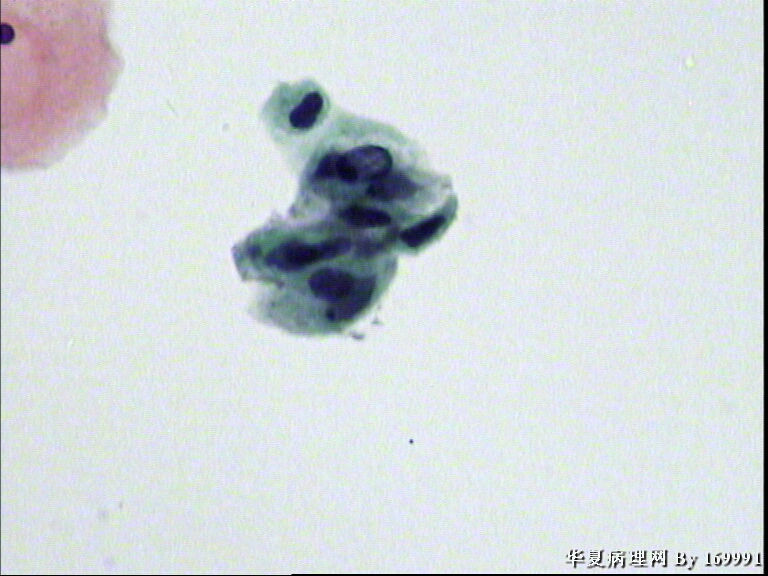

宫颈液基,患者,23岁,宫颈中糜

感觉像高级别,但患者年龄太小。ASC-H

大家都看得不错。最高可能是CINII级,看活检了。

HSIL可能已经原位癌了

我感觉报HSIL有点高了,就细胞的形态来看,核增大深染的基本上还是中层以及接近表层的细胞,结合患者年龄,我认为报LSIL更好一些。不知道对不对,请各位老师指教啦!